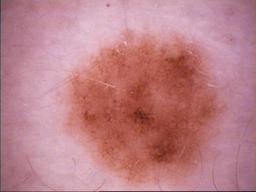

{

"age_approx": 35,

"anatom_site_general": "anterior torso",

"concomitant_biopsy": false,

"diagnosis_1": "Benign",

"diagnosis_2": "Benign melanocytic proliferations",

"diagnosis_3": "Nevus",

"diagnosis_4": "Nevus, NOS, Compound",

"diagnosis_confirm_type": "serial imaging showing no change",

"image_type": "dermoscopic",

"melanocytic": true,

"patient_id": "IP_0719280",

"sex": "female"

}